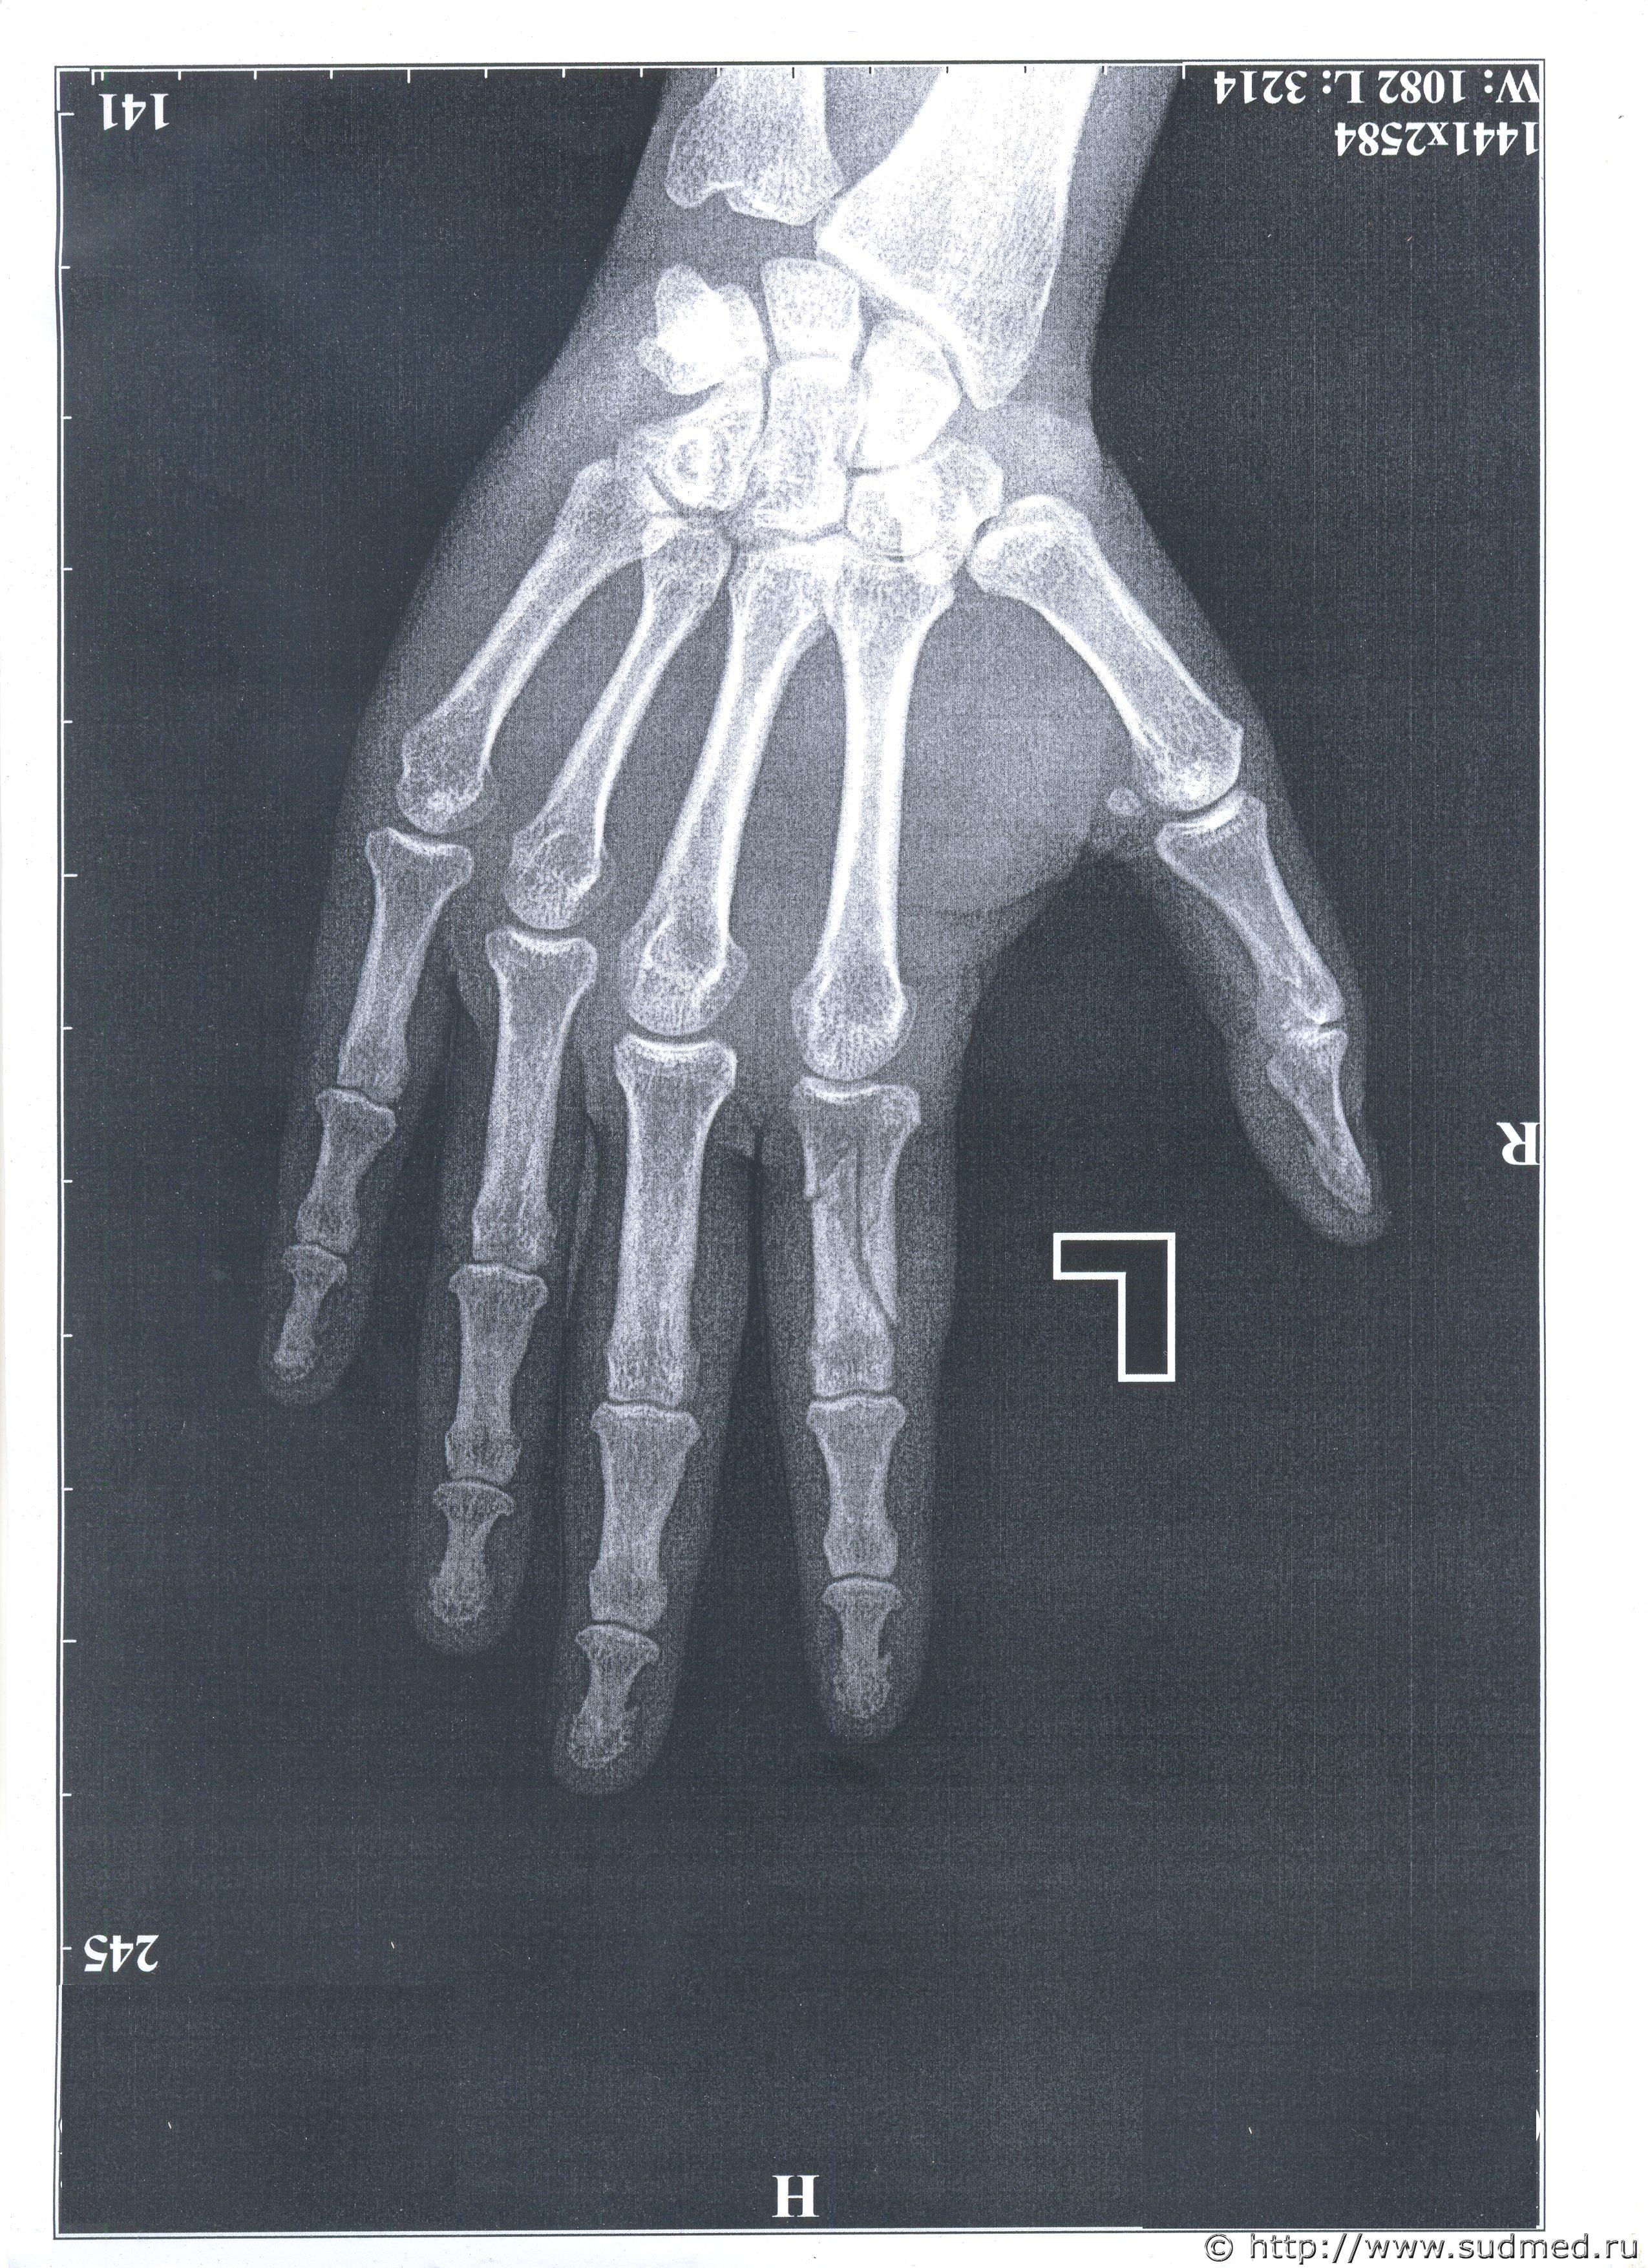

Добрый день. Как именно нужно упасть, что бы поломать палец таким образом. Падение из положения стоя. Оскольчатый перелом со смещением. Я - потерпевшая, закрывала голову рукой, по которой били пивной кружкой. Ответчик с адвокатом утверждают, что я упала таким образом. Заранее спасибо.Судебная медицина - Прикрепленное изображение Судебная медицина - Прикрепленное изображение

Работа у адвокатов такая - за деньги подонкам помогать. То что они говорят, абсолютная чушь. На снимке совершенно очевидно,что такой перелом не мог образоваться от осевой нагрузки, а "упасть" и получить такое действительно сложно. Пусть детально соврут, подпишут, и потом через ходатайство потребовать поставить вопрос эксперту об установлении механизма образования перелома и возможности его получения при обстоятельствах и по механизму указанного подозреваемым (а в конце - если возможно и при обстоятельствах указываемых пострадавшей - то по какому механизму наиболее вероятно). Уверен, бредовую идею о падении, даже среднего уровня медицинский криминалист разобьет в легкую.

Формирование оскольчатого перелома характерно для ударного воздействия тупого твердого предмета в проекции перелома. Так, как Вы написали, т.е. от удара кружкой по основной фаланге указательного пальца, который был прижат к голове, этот перелом вполне мог возникнуть. Хрестоматийный пример. При падении такой перелом мог бы образоваться только при стечении ряда уникальных обстоятельств. При падении с упором на ладонь или на кончик указательного пальца такой перелом принципиально не может образоваться.

Добры день, уважаемые эксперты. Был перелом руки. Прикрывала голову рукой,а по ней ударяли кружкой. Подозреваемый выдвинул версию, что я упала так, потом обогатил ещё тем, что я так махала рукой, что могла задеть за стол или его пивную кружку - и поломать руку.Прикладываю рентген и выдержки из двух экспертиз. Очень большая просьба объяснить - что такое

1) "действие травмирующей силы по оси пальца"

2) " контактный ПРЯМОЙ удар"

И ещё очень непонятна фраза - "установленный перелом мог образоваться при любых условиях, допускавших контактное взаимодействие поврежденной фаланги пальца и поверхности травмирующего предмета" - тут понятно, что естественно, если хорошо размахнуться- то можно - но степень "хорошо" должна быть определенная.

"По оси пальца" - то есть вдоль самого пальца (удар кончиком выпрямленного пальца или по кончику пальца - как, например, с большой силой "ткнуть" выпрямленным пальцем в стену или т.п., либо сильно ударить чем-то по выпрямленному пальцу - нередко в баскетболе так бывает, когда неудачно приходит мяч) или вдоль оси основной фаланги, если палец согнут.

"Контактный прямой удар" - ударное воздействия тупого твердого предмета в проекции перелома. Именно то, о чем Вы пишите - удар пивной кружкой по месту перелома, когда палец лежал на голове.

Прочность основной фаланги указательного пальца сопоставима с прочностью куриной бедренной кости. Если не лень экспериментировать, то можете попробовать самостоятельно оценить достаточность условий для её перелома: это явно не "обычное" эмоциональное размахивание руками.